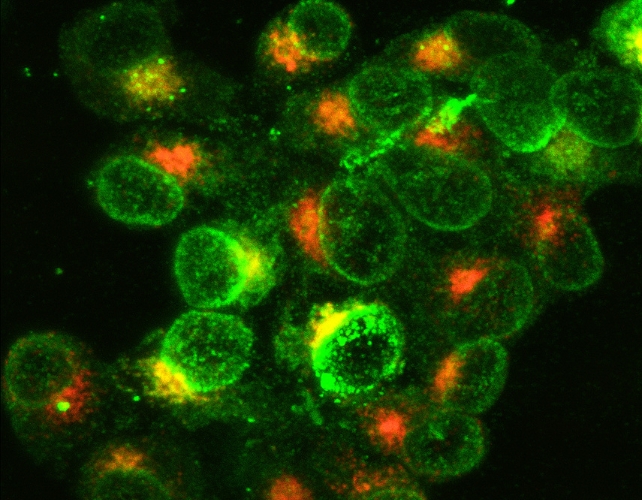

Beyond this autoimmune perspective, a growing number of novel and diverse theories are gaining traction. For instance, some researchers propose that Alzheimer’s is intrinsically linked to a malfunction of mitochondria, the vital energy-generating organelles found within every neural cell.

Mitochondria are responsible for metabolizing inhaled oxygen and ingested glucose into the energy essential for cognitive functions such as memory and thought processes.

Other researchers suggest that the condition may be the ultimate consequence of a specific cerebral infection, with oral bacteria frequently implicated as potential causative agents. Furthermore, some scholars posit that the disease might originate from an improper regulation of trace metals within the brain, including but not limited to zinc, copper, or iron.

It is a cause for encouragement to witness the emergence of fresh perspectives on this long-standing ailment. Currently, dementia impacts over fifty million individuals globally, with a new diagnosis occurring every three seconds.